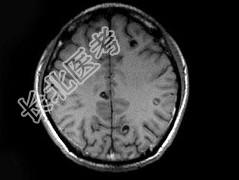

- 单项选择题男,29岁, 头痛不适半个月,MRI扫描如图, 最可能的诊断是 ( )

A、脑转移瘤

B、脑囊虫病

C、脑弓形虫病

D、脑脓肿

E、未见异常